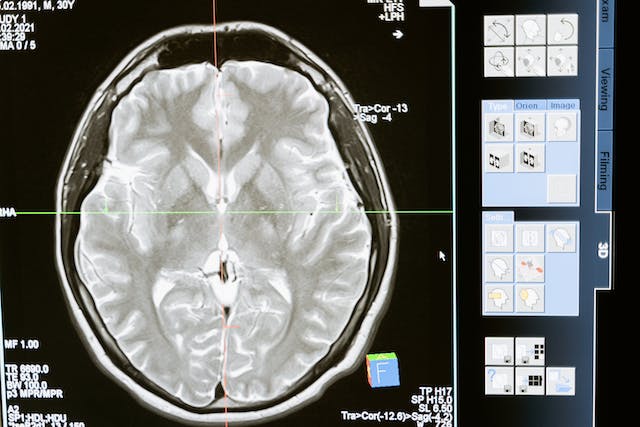

진단방법

뇌전증의 진단은 주로 증상, 신체검사, 그다음 단계로 아래와 같은 추가적인 진단 검사가 이루어져요.

- 뇌파 검사 (EEG): 이 검사는 뇌의 전기 활동을 측정하여 비정상적인 패턴을 찾아냅니다. 뇌전증에서는 특정한 뇌파 패턴이 종종 나타나므로, 이를 통해 뇌전증의 진단에 중요한 단서를 얻을 수 있어요.

- 영상 진단 검사: MRI, CT, PET 등의 영상 진단 검사를 통해 뇌의 구조적 이상을 찾아낼 수 있습니다. 이러한 검사는 뇌의 손상, 종양, 뇌혈관 이상 등을 확인하는 데 도움이 돼요.